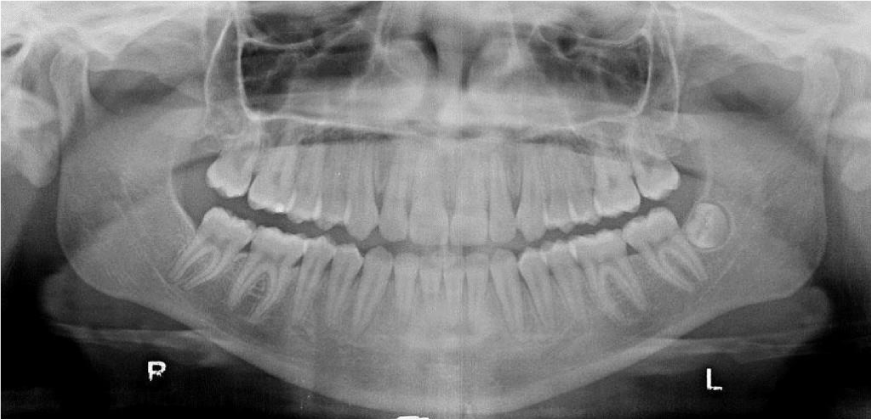

Panoramic radiographs showed the presence of two impacted canines. Considering the good morphology of the teeth, the position and the absence of ankylosis, in agreement with the oral surgeon the surgical orthodontic disimpaction was decided (Figure 1d).